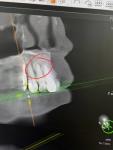

Здравствуйте, прохожу протезирование коренных зубов. КТ показало образование на корнях зубов 12 и 43. Врач затрудняется ответить что это может быть.

Вверху предположительно цементома, а внизу предположительно одонтома. Это все доброкачественные состояния. У вас получится прислать все содержимое диска с КТ через файлообменник, например, гугл-диск?

Мой лечащий врач склонен считать что это цементно костная дисплазия и в верху и внизу. Предлагает не трогать и смотреть в динамике как образование будет себя вести в дальнейшем (это вверх). Низ просто под наблюдением, там коронок не будет. Если будет рост на корне 12, возможна резекция корня с последующей гистологией. Как бы решать проблему по мере поступления.